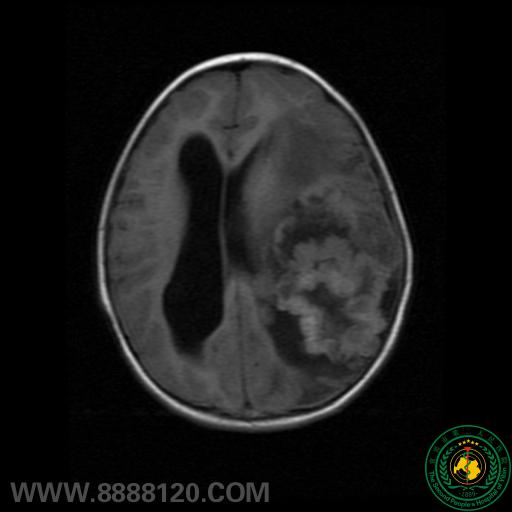

患者头颅MRI示:左侧额颞顶叶巨大不规则混杂信号团块,中线结构明显右移,颅骨明显受侵犯。